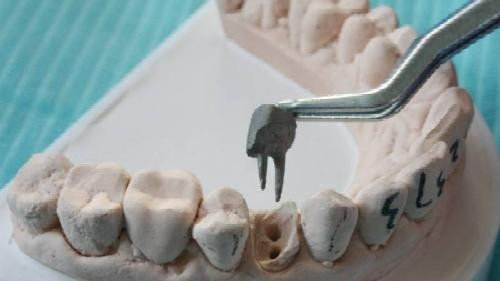

2、揭開髓腔:去凈腐質(zhì)和原有充填物、揭凈髓頂,看到整個(gè)髓底解剖結(jié)構(gòu)以便后續(xù)調(diào)節(jié)順利進(jìn)行。

3、確定根管工作長(zhǎng)度:應(yīng)用平行投照X線方法、根管長(zhǎng)度測(cè)量?jī)x確定根管度,好插針拍X片。

4、根管預(yù)備:根管清理成形的目的是去凈根管壁上的感染物,通過(guò)根管器械的切削作用去除感染的牙本質(zhì)并清理根管壁細(xì)菌以利于根管充填。